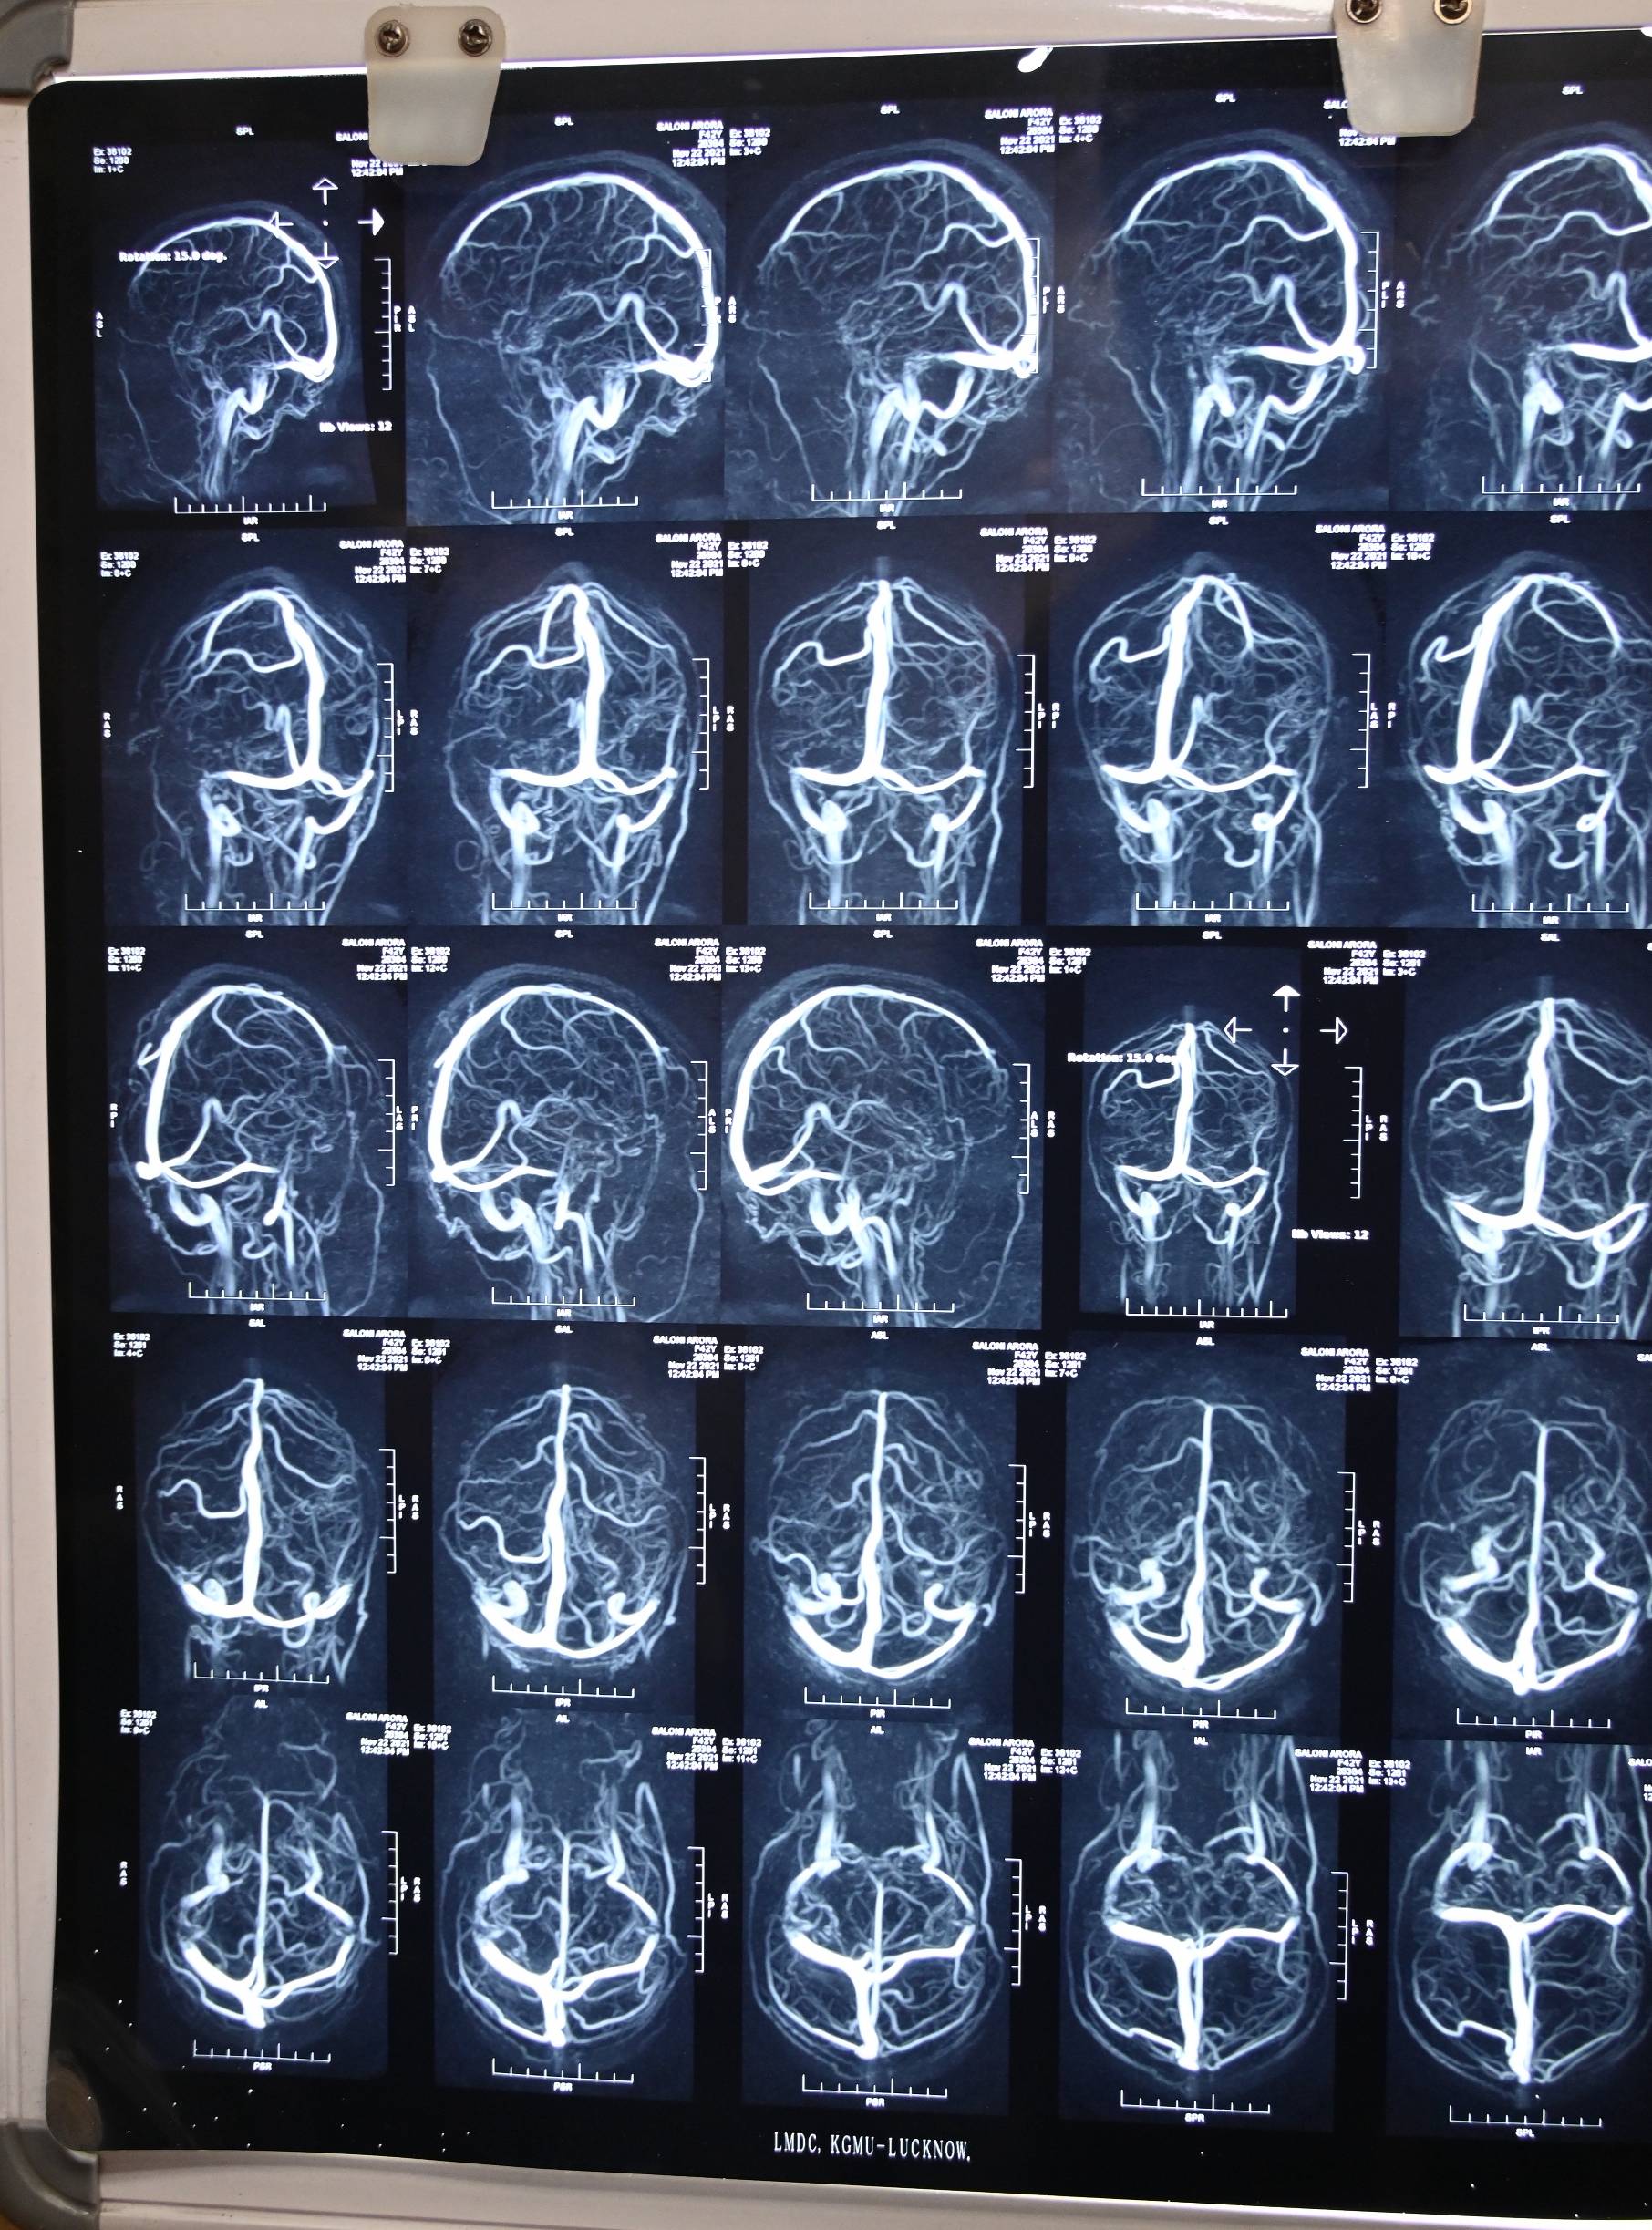

There is no Csf leak for many months. She got advised to undergo CT cisternography to rule out any remaining defect.

She awas again advised for the Ct cisternography but our of fear or anxiety she is postponing the investigation, which is crucial in determining the cure.

Dr Ravi talked with patient over the zoom call on 18th March 2024. She got cured for her CSF Rhinorrhea trouble. For last 10 months she never experienced any single drop of CSF leak. She got advised for its prognostic lab test CT cisternography, but she is constantly making some excuses for the same. Her migraine trouble also got cured.